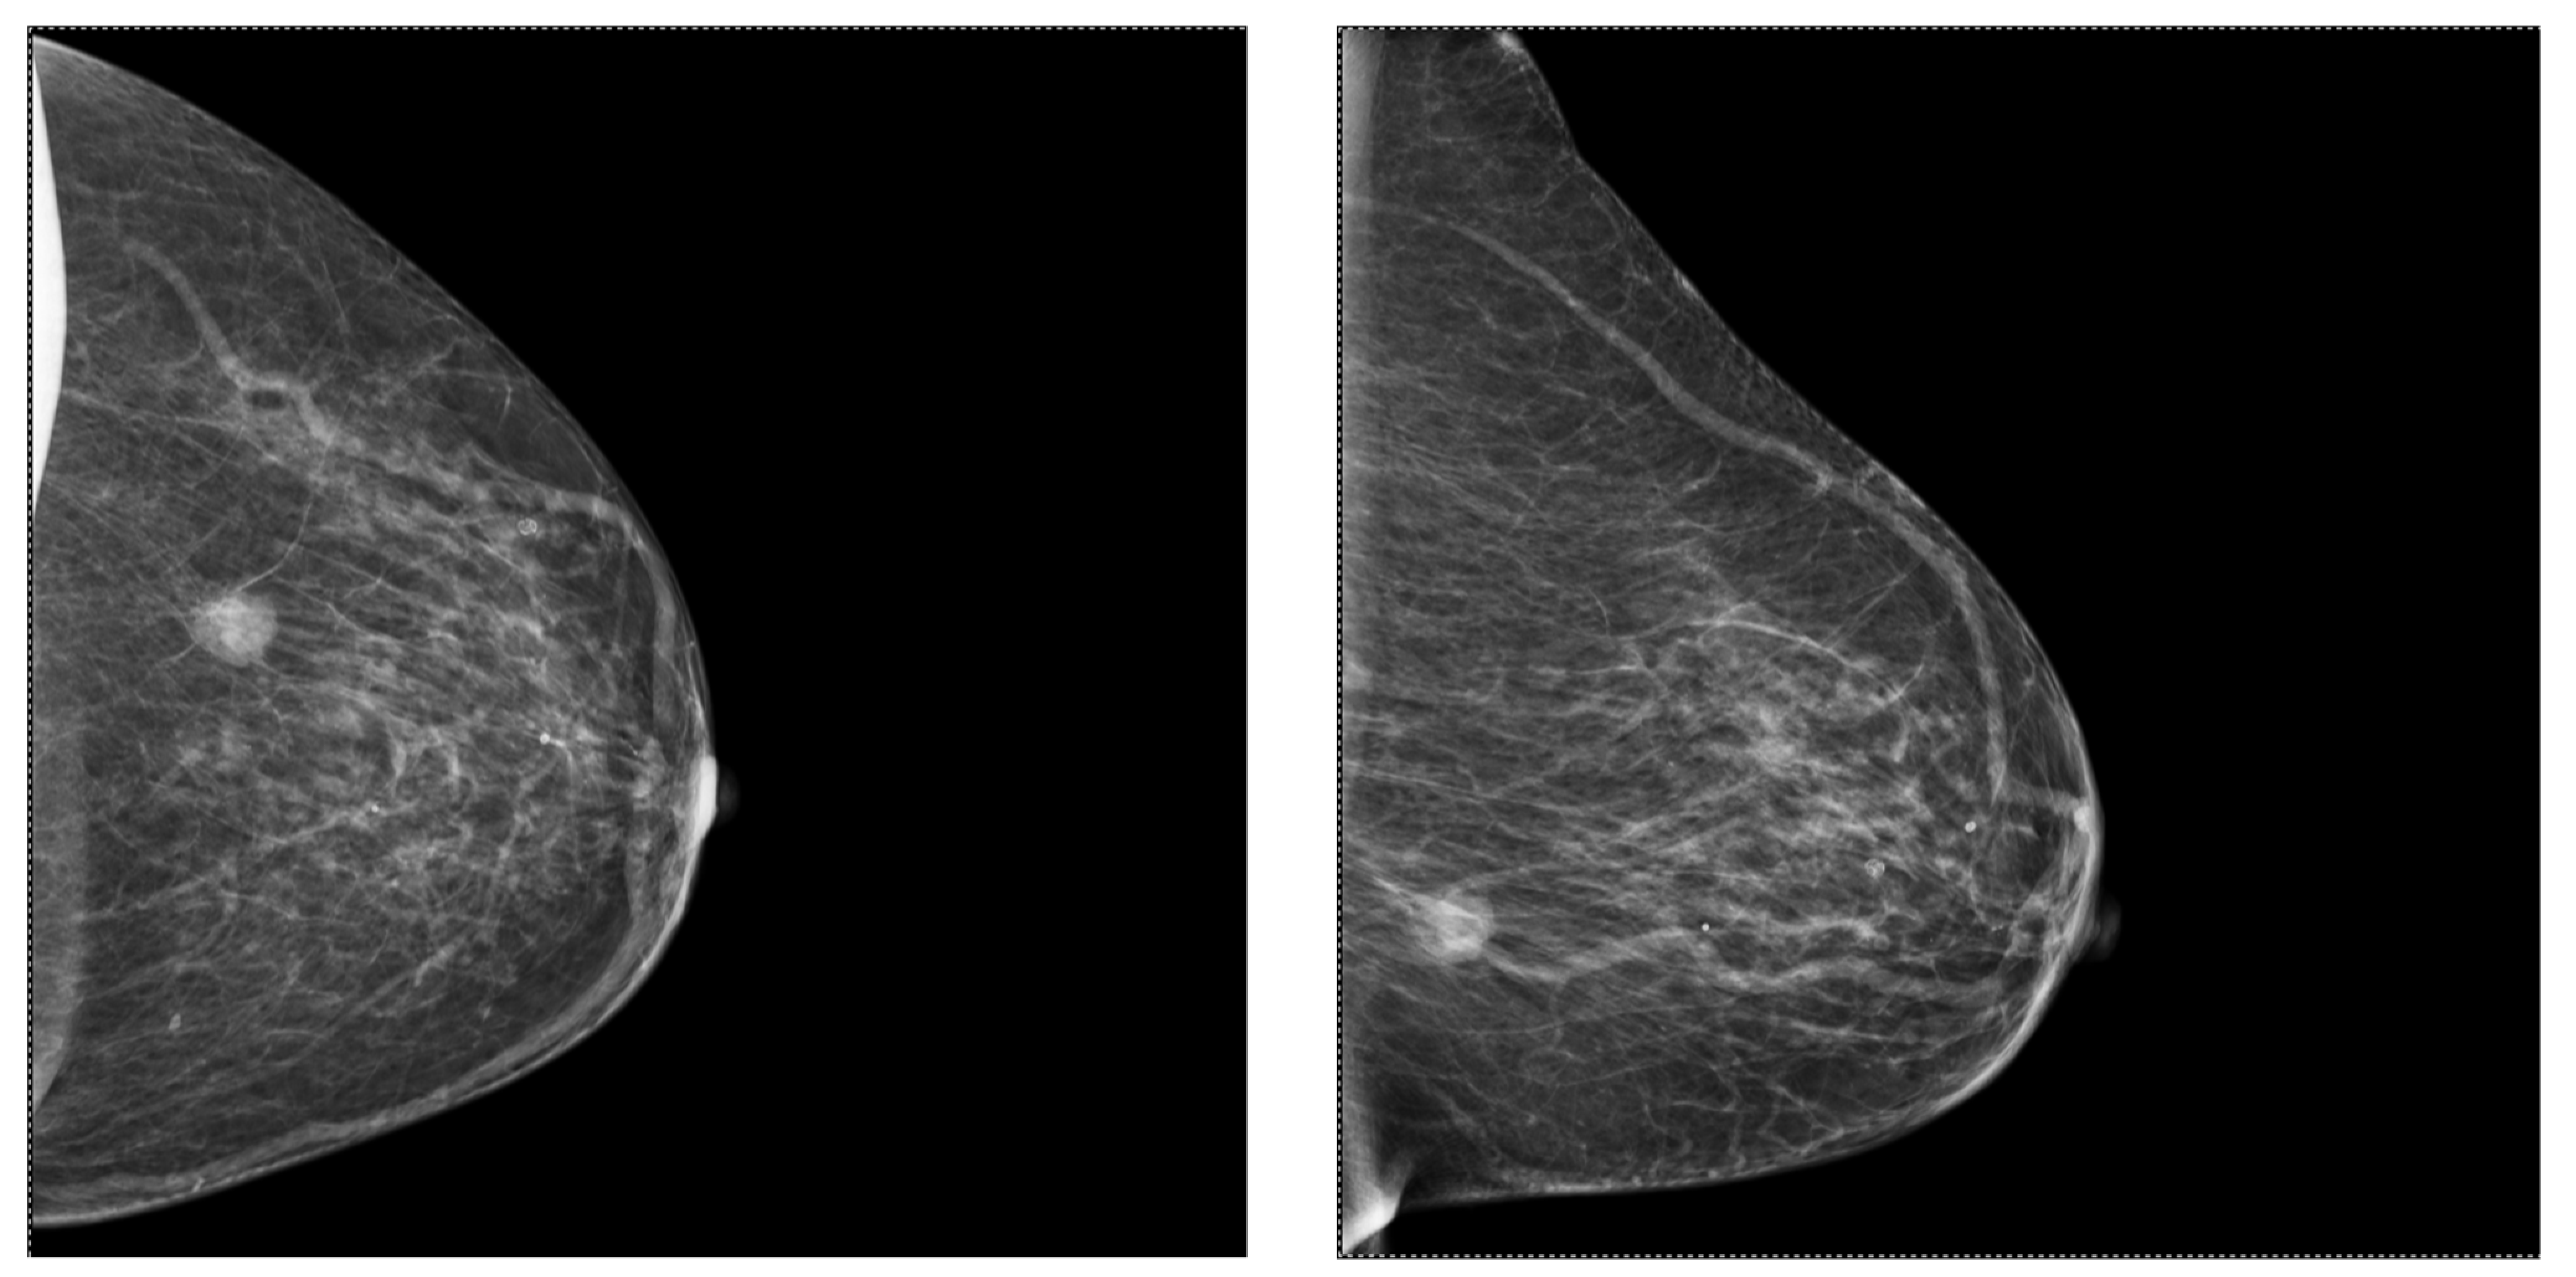

2.2. Mammography (MG)